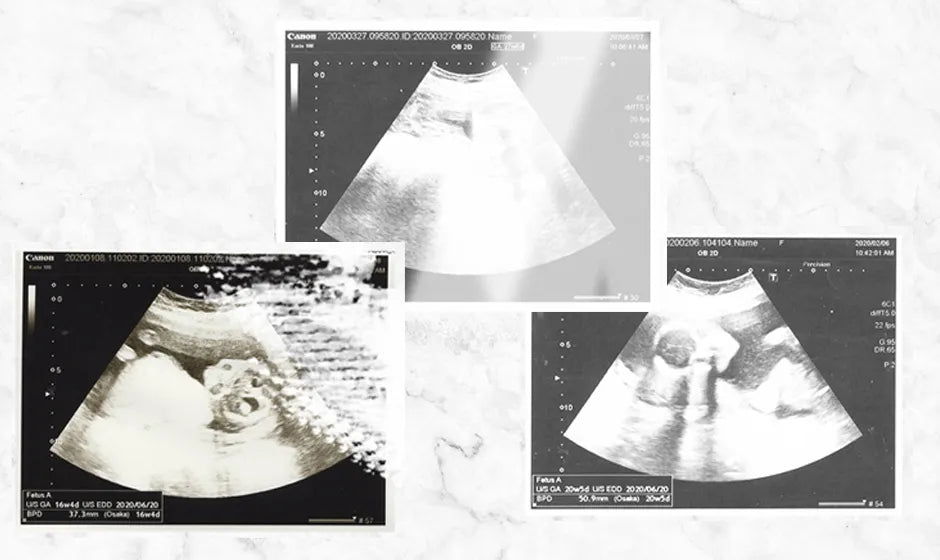

エコー写真ポスターを400件以上制作してきた当社には、毎日たくさんのエコー写真が届きます。その中で、色褪せの進行度は本当にさまざまです。この記事では、実際に届いたエコー写真の状態をもとに、色褪せる原因と今すぐできる対策をご紹介します。